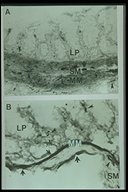

Increased acetylcholinesterase activity in Hirschsprung's disease, thick staining is observed in mucosa and submucosa layer (LP: lamina propria, MM: muscularis mucosae, SM: submucosa)